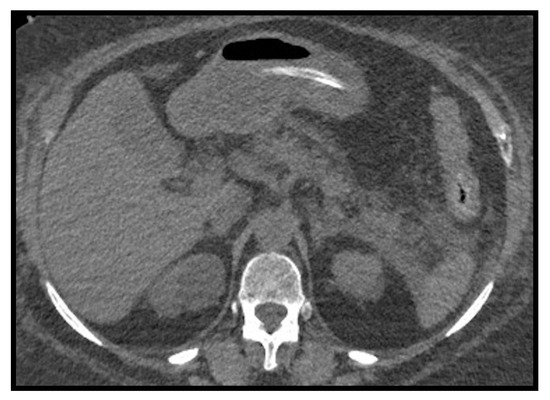

4. Adult “Abdominal” COVID-19

In recent times, the efforts of the international scientific community aimed to define the abdominal manifestations of COVID-19, even if there is a small number of studies published on this topic. Although the pathogenetic mechanisms have yet to be clarified, we know that SARS-CoV-2 enters cells by exploiting the ACE-2 receptor which is widely expressed in the GI tract, pancreas, biliary tract and vascular endothelium [46,47,48]. It is also known that critical patients with COVID-19 have systemic coagulopathy and a thrombotic diathesis supported by the important underlying inflammatory process [48,49,50,51]. Although pulmonary embolism is the most frequent thrombotic complication in these patients, arterial thrombosis could be equally relevant and its presentation as acute aortic occlusion would be evocative [52]. Baeza et al. [53] presented three cases of acute aortic occlusion (AAO) and concluded that despite the pre-existence of risk factors in these patients, there is likely an association between COVID-19 infection and the development of a prothrombotic state leading to significant arterial complications (Figure 11).

Figure 11. Case of acute aortic parietal thrombosis in patient affected by SARS-CoV-2 pneumonia. Image (A) shows the lung’s involvement caused by COVID-19 pneumonia. Thromboembolic opacification defect of a segmental (anterior) arterial branch for the right lower lobe is associated (B). (C) Axial images of subrenal acute aortic thrombosis. In coronal image (D) is it possible to notice the acute aortic thrombosis which extends craniocaudally for about 6 cm. (E) Complete resolution of aortic thrombosis after therapy.